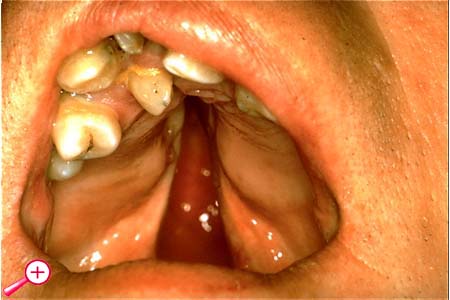

Das Vollbild dieser Missbildung ist die totale Spalte des gesamten Gaumens.